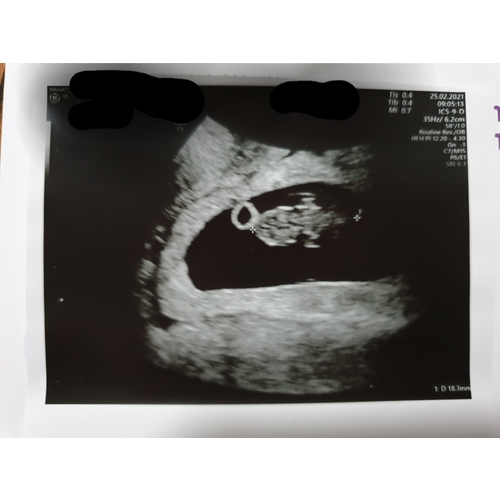

Volgens de Ramzi methode wordt er op deze manier voorspelt welk geslacht je krijgt.

Ligt je placenta aan de linkerkant van je lichaam?

Dan verwacht je waarschijnlijk: een meisje!

Bevindt je placenta zich aan de rechterkant van je lichaam?

Dan groeit er in je buik waarschijnlijk: een jongen!

Placenta ligt rechts

Volgens de methode zou je dan een jongen krijgen

Het is jammer dat je niet hebt gevraagd welke kant de placenta zit. Want het kan namelijk zijn dat de echo gespiegeld word weer gegeven.

Inwendige echo: Zie je op de uitdraai van een inwendige echo de lichte vlek rechts in de baarmoeder? Dan verwacht je volgens de Ramzi-theorie een jongen. Wanneer je hem links in de baarmoeder ziet, zou je van een meisje in verwachting zijn.

Uitwendige echo: Als de echo via je buik is gemaakt, is de echo gespiegeld. Zie je op de uitdraai van de echo de lichte vlek rechts? Dan zou dit betekenen dat je een meisje krijgt. Een lichte vlek aan de linkerkant wijst bij een uitwendige echo op een jongen.

Na aanleiding wat hierstaat zou je inderdaad een jongen krijgen.